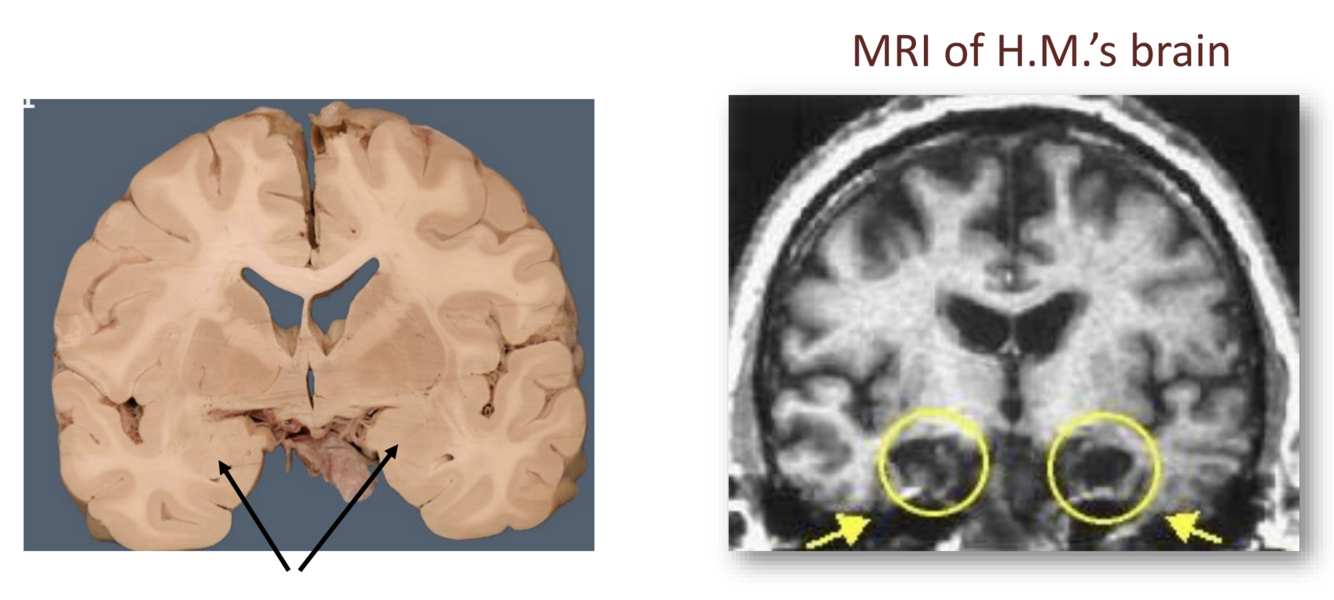

• Severe epilepsy

• removed hippocampus to reduce/treat epilepsy

• Epilepsy starts in a localized region of the brain. So, removing this localized region to treat epilepsy. THis is still done to this day - vast improvement.

• Often these start in the medial temporal lobe (which is near the hippocampus)

• Typically remove the MTL tissue and tge hippocampus tissue in one lobe. Not too bad of deficits because they still have the other side functional.

• In H.M, they removed the medial temporal lobes on both sides. After surgery, could not form any new memories. Still had old memories, just could not make new memories.